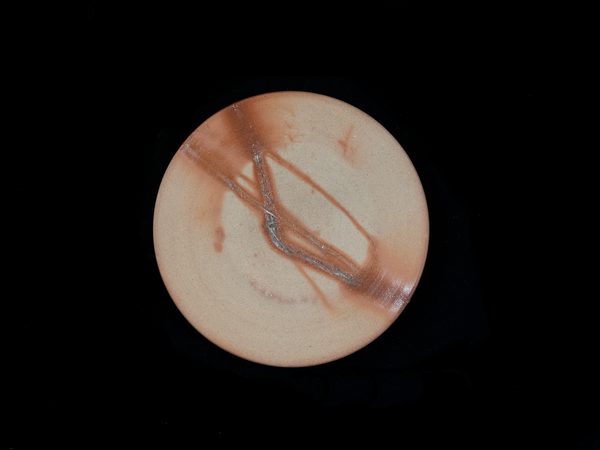

This pour over set comes with four pieces: the stand, dripper, mug, and ramekin. It displays the traditional Bizen beauty, a pattern developed by the natural ash that falls on the clay pieces and the direction of the flames and shadows inside the kiln during the firing process. This piece is designed for brewing and holding hot coffee and the thickness of the clay walls helps retain heat and be manageable to hold. The stand is made out of solid, well-joined and oiled walnut slabs in a contemporary design. The dripper uses paper filters and it is recommended to crease the filters in a way to better fit within the walls. The ramekin can be used to catch the final drips after the coffee is brewed or as a dish for milk and cream.

*The photos are indicative of the general look of these, but, as there are many samples, there may be a slight variation from product to product